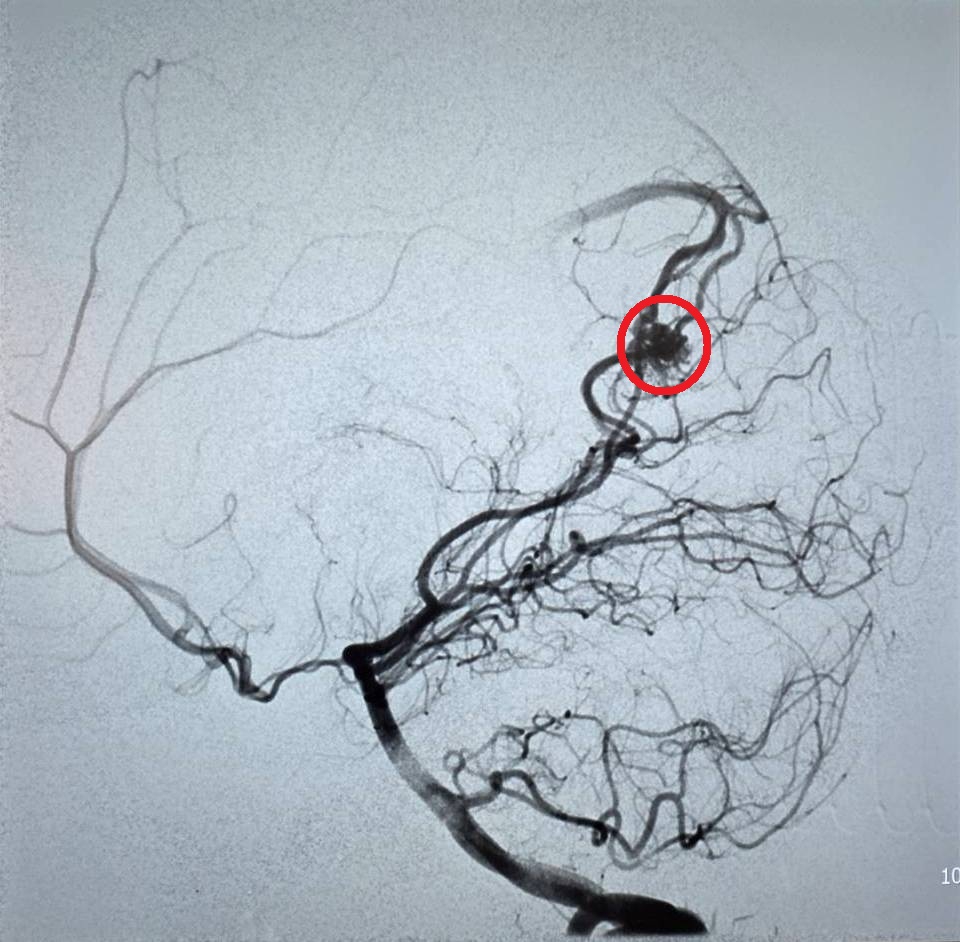

(特派員劉鳳瑩、陳明/苗栗報導)23歲的周小姐正值青春年華,日前卻在毫無預兆下感到一陣劇烈頭痛,隨即伴隨嚴重的頭暈與嘔吐感,家屬見狀趕緊將她送往大千綜合醫院急診。經腦部電腦斷層掃描,醫師赫然發現其左側腦部有出血跡象,且出血位置極其不尋常。醫療團隊隨即展開精密檢查,證實為罕見的「顱內動靜脈畸形」引發出血。所幸在神經放射科康靜維醫師及時進行微創血管內栓塞治療後,順利止住出血,病人症狀明顯改善,成功化解一場腦內危機。

大千綜合醫院神經放射科康靜維醫師指出,「顱內動靜脈畸形」是一種先天性的腦血管病變。在胚胎發育過程中,若動脈與靜脈之間缺乏微血管緩衝,導致高壓的動脈血流直接衝入脆弱的靜脈,管壁便會因長期無法負荷壓力而逐漸薄弱,最終像吹太大的氣球一樣破裂,引發腦出血。這種疾病好發於30歲左右的年輕族群,臨床表現以腦出血最為常見,但也可能出現癲癇或長期慢性頭痛等症狀。

康靜維醫師表示,顱內動靜脈畸形若未及時診斷與治療,每年約有1%至3%的出血風險。目前的治療技術已相當多元且成熟,主要包含:

1.微創血管內栓塞:透過導管進入血管,精準封堵畸形處。